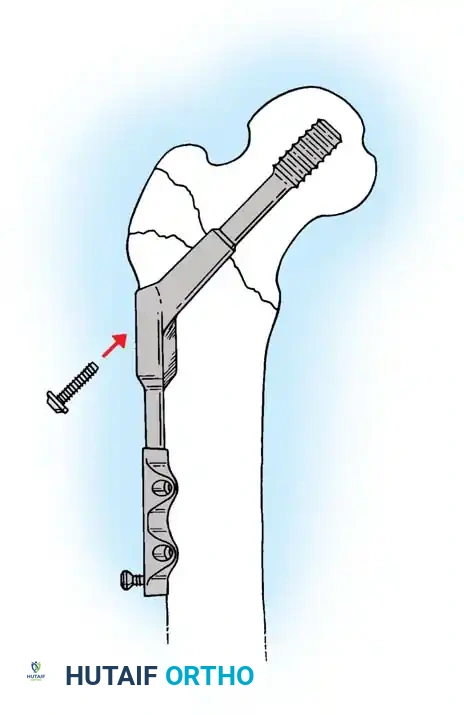

5. Intramedullary Nailing (For Unstable Fractures)

If a cephalomedullary nail is chosen, the entry point is established at the tip of the greater trochanter (or slightly medial, depending on the specific implant design).

Insertion of the cephalomedullary nail down the femoral shaft. Care must be taken not to distract the fracture site during insertion.

After the nail is seated, the proximal lag screw(s) are inserted through the nail into the femoral head, adhering to the same TAD principles.

Proximal locking of the cephalomedullary nail. The targeting guide ensures accurate trajectory into the femoral neck.

Finally, distal locking screws are placed to control rotation and maintain length.